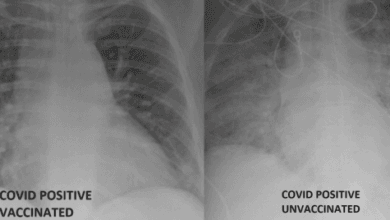

Radiografía revela diferencias entre pulmón de pacientes con y sin vacuna del Covid-19 (Foto)

Estas radiografías revelan la diferencia que hacen las vacunas contra el Covid-19, con pulmones desprotegidos devastados por el virus. Un…